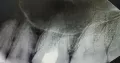

Три года назад лечили зуб от кариеса, удалили все нервы с 4-го раза (долго искали последний). Далее зуб стал периодически побаливать и реагировать на холодное и горячее (задний верхний справа). Через 1,5 года пошла в другую клинику, сделали три раза рентген, ничего не нашли, гайморовые пазухи чистые. Отправили на КТ — тоже ничего.

Врач сказал, что зуб хорошо сделан. Удалил чуток нависающей пломбы и отпустил. Зуб несколько недель не беспокоил. Вчера зуб резко заболел, и теперь при ходьбе сильно дергает нерв, не могу понять в каком зубе. При этом несколько дней назад, без температуры, переболела сильным насморком. Сейчас состояние такое, что отдает в ухо, затылок справа и вся правая сторона ноет.

Откровенно говоря, причина боли мне не известна и не понятна. Возможно, прорезывается восьмой зуб, так как присутствуют характерные симптомы (отдает в ухо и голову). Необходимо тщательно вас осмотреть. Проверить наличие дополнительного ответвления канала в ранее пролеченном зубе, а также проверить соседние зубы.